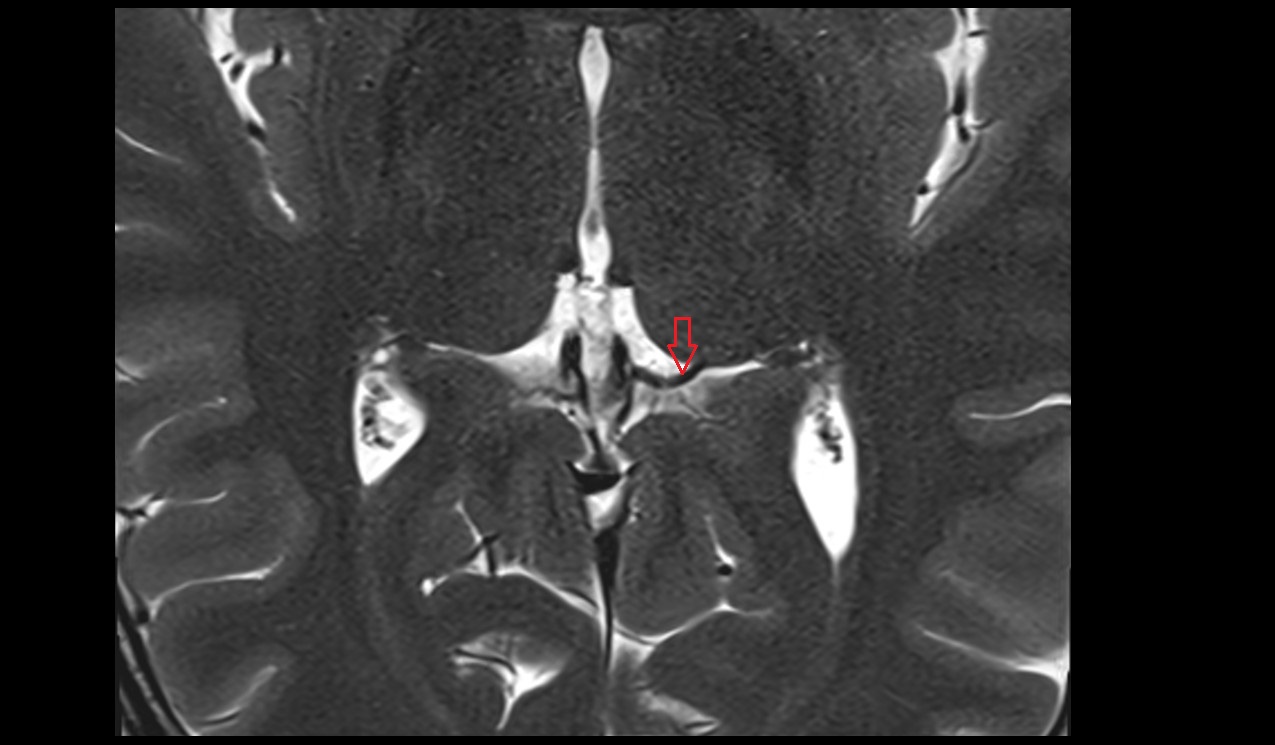

- Peripheral zone of prostate

- Anterior Fibromuscular Stroma of prostate

- Central zone of prostate

- Transitional zone of prostate